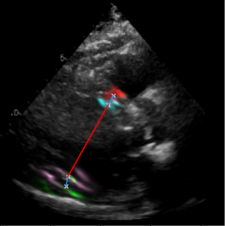

| (a) LV Measurements | (b) Label Smoothing |

Left Ventricular Hypertrophy (LVH), one of the leading predictors of adverse cardiovascular outcomes, is the condition where heart’s mass abnormally increases secondary to anatomical changes in the Left Ventricle (LV) [10]. These anatomical changes include an increase in the septal and LV wall thickness, and the enlargement of the LV chamber. More specifically, Inter-Ventricular Septal (IVS), LV Posterior Wall (LVPW) and LV Internal Diameter (LVID) are assessed to investigate LVH and the risk of heart failure [21]. As shown in Figure 1 (a), four landmarks on a parasternal long axis (PLAX) echo frame can characterize IVS, LVPW and LVID, and allow cardiac function assessment. To automate this, machine learning-based (ML) landmark detection methods have gained traction.

It is difficult for such ML models to achieve high accuracy due to the sparsity of positive training signals (four or six) pertaining to the correct pixel locations. In an attempt to address this, previous works use 2D Gaussian distributions to smooth the ground truth landmarks of the LV [9, 13, 18]. However, as shown in Figure 1 (b), for LV landmark detection where landmarks are located at the wall boundaries (as illustrated by the dashed line), we argue that an isotropic Gaussian label smoothing approach confuses the model by being agnostic to the structural information of the echo frame and penalizing the model similarly whether the predictions are perpendicular or along the LV walls.